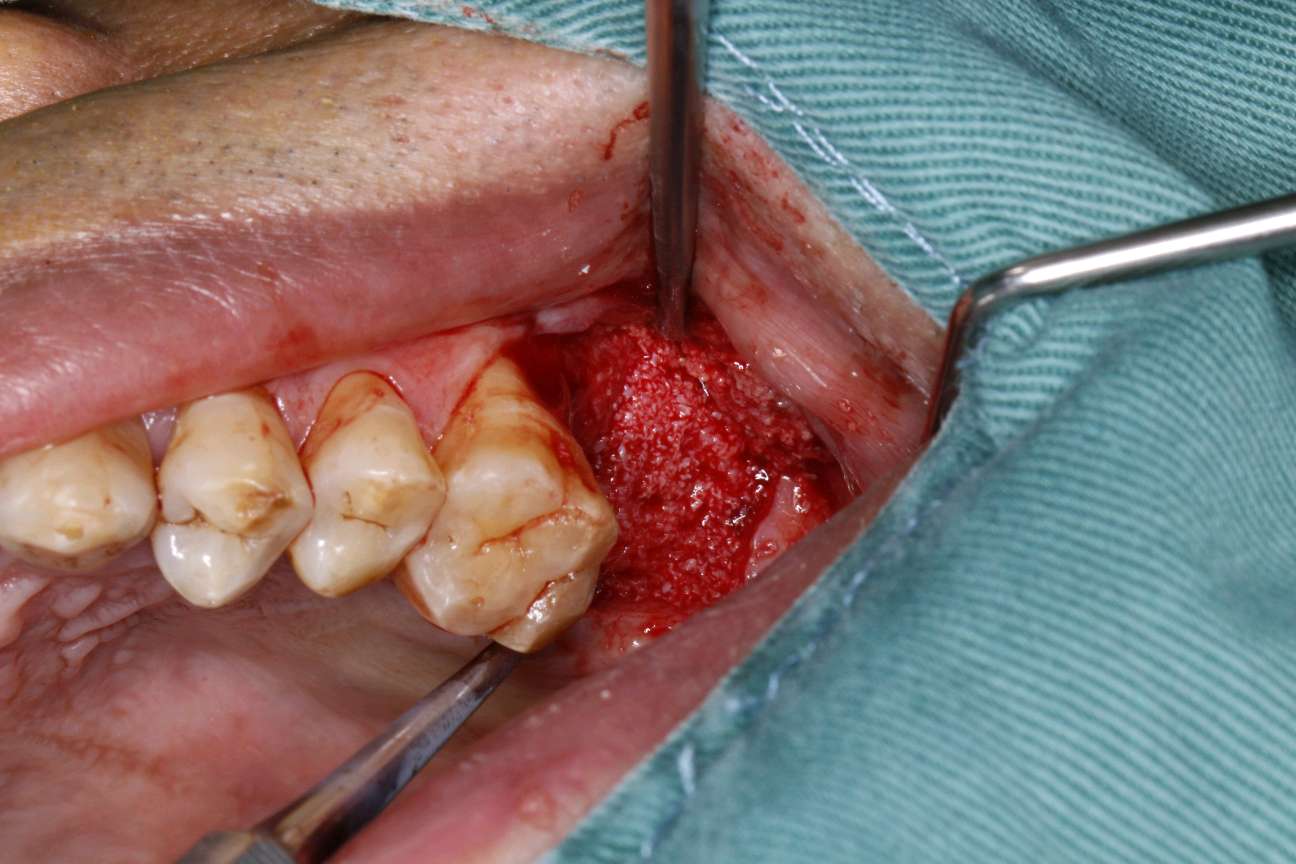

患者知情同意下,抽静脉血30ml,制作 CGF ,0.1%聚维酮碘溶液口内粘膜消毒,0.5%聚维酮碘溶液口外皮肤消毒,4%盐酸阿替卡因肾上腺素注射液2.0ml浸润麻醉,牙槽嵴顶切开粘骨膜,翻瓣。见腭侧大面积骨缺损,球钻定位,先锋钻导向,骨质钻扩大种植窝,行上颌窦内提,特殊冲顶器械敲击,抬高上颌窦底部骨质和黏膜。并攻丝植入 ITI 种植系种植体4.8*8mm,上封闭螺丝,腭侧骨缺损区植 bio - oss 骨粉0.25g及 CGF ,并盖 bio - Gide 膜及 CGF 膜,严密缝合,常规医嘱,15天拆线,抗生素自备。